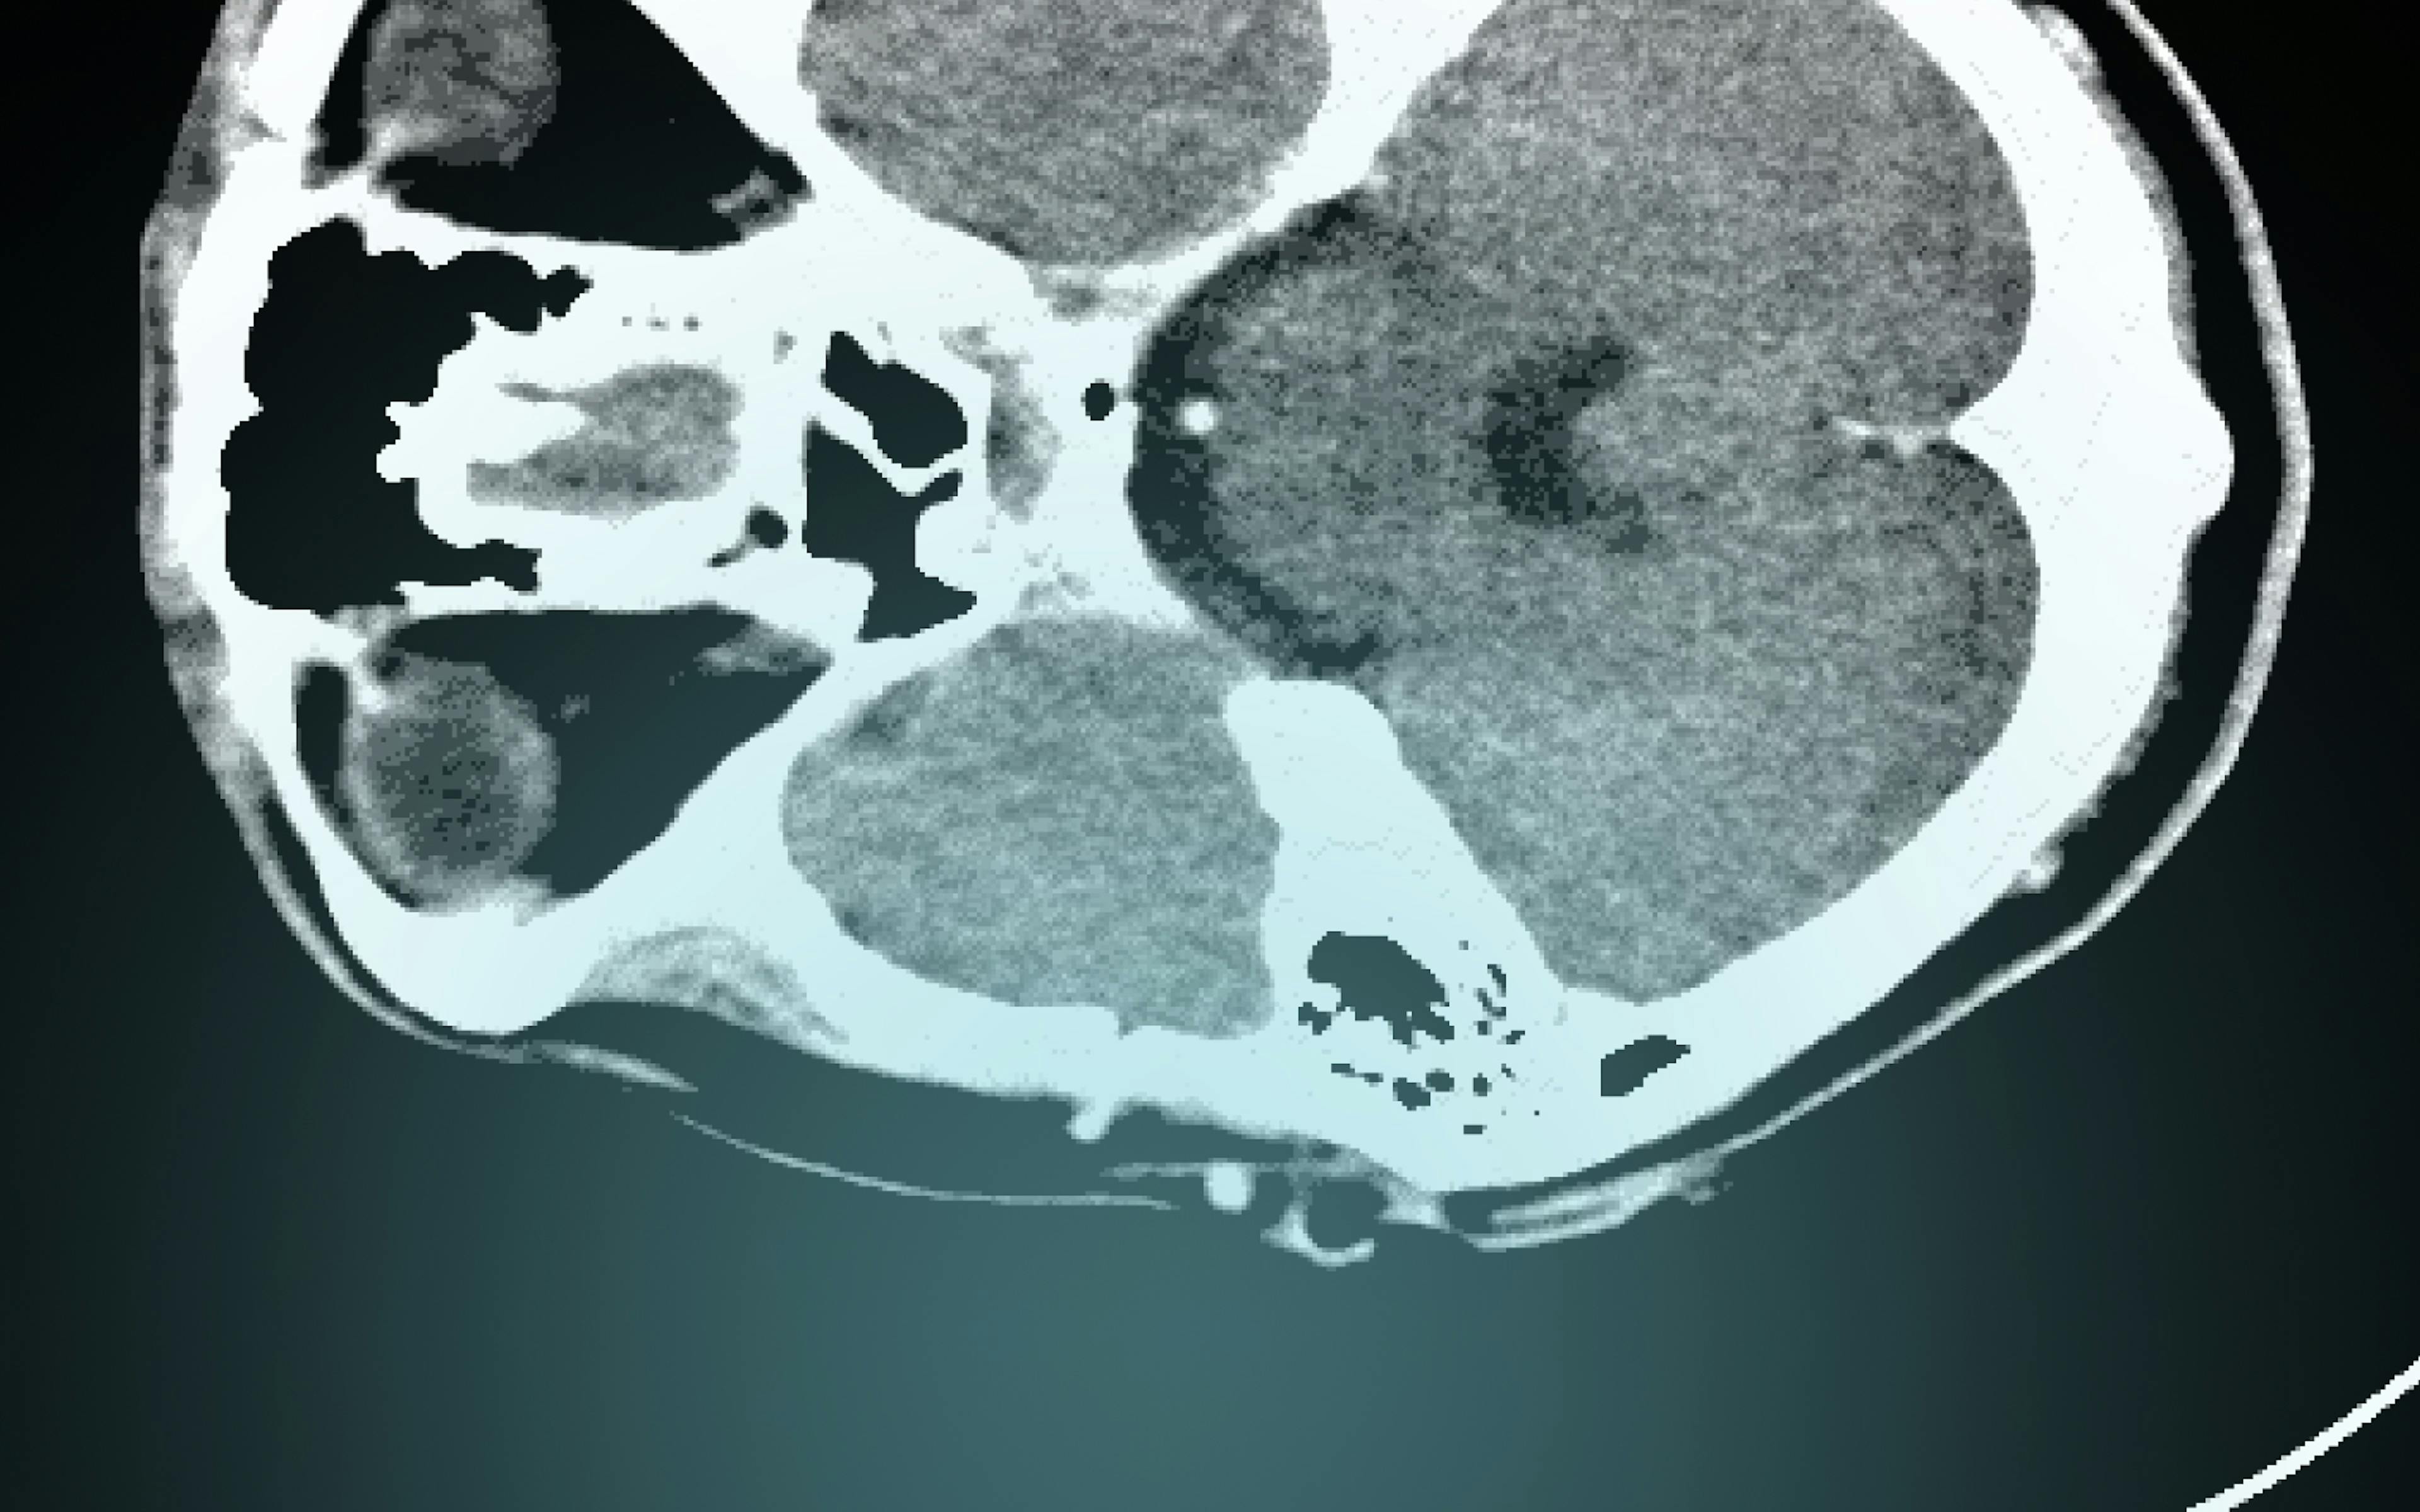

Coronial investigations into sudden, unnatural, violent and accidental deaths occupy an important role in the Australian legal system. They require coroners to ascertain the identity of the deceased, determine the cause of a death and in many instances, make recommendations for reducing the occurrence of preventable deaths. A key element of the Australian coronial investigation has been the invasive autopsy, which is performed by a forensic pathologist if a coroner deems it necessary for determining the medical cause of death. In recent decades, the autopsy has become a site of contestation, especially for families of the deceased who oppose post-mortem dissections due to religious or cultural beliefs. Since the late twentieth century, forensic imaging technology, particularly post-mortem computed tomography (CT), has offered the ideal of a non-invasive, permanent, virtual autopsy.

This project examines how forensic imaging technology impacts coronial investigations in Australia. It focuses on how post-mortem CT has been used since the late twentieth century to supplement or as a triage for invasive autopsies for the purposes of identifying the deceased and determining the medical cause of a death. Little is known about how technological modifications to death investigations assist or hinder practitioners in fulfilling their statutory responsibilities under coronial law. The project thus aims to analyse how forensic imaging technology has transformed coronial investigations since the twentieth century and how it continues to affect the way coroners, pathologists, radiologists and other medico-legal personnel working in the jurisdiction perform their roles in the legal system. If the use of post-mortem CT is to be expanded in Australia, then it is critical to these debates that we examine the social and legal effects of the implementation of forensic imaging technology in coronial investigations.